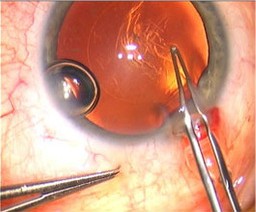

1、手术前,撑开眼睑

2、在角巩膜缘做切口

3、人工撕囊